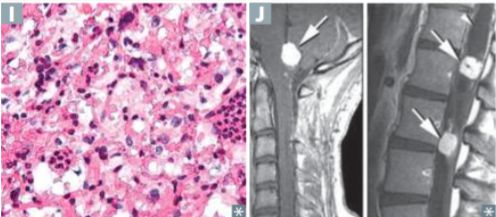

Which feature of von Hippel-Lindau disease is seen in the image below? _____